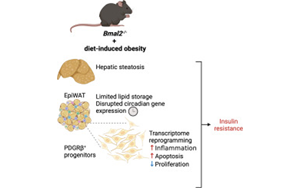

BMAL2調(diào)控肥胖期間脂肪組織炎癥與代謝適應的機制研究

綜述揭示了晝夜節(jié)律核心轉(zhuǎn)錄因子BMAL2通過調(diào)控脂肪前體細胞命運和TNFα介導的炎癥反應,影響脂質(zhì)儲存分布與胰島素敏感性的新機制,為肥胖相關代謝疾病(如T2D和MASH)的防治提供了關鍵靶點。